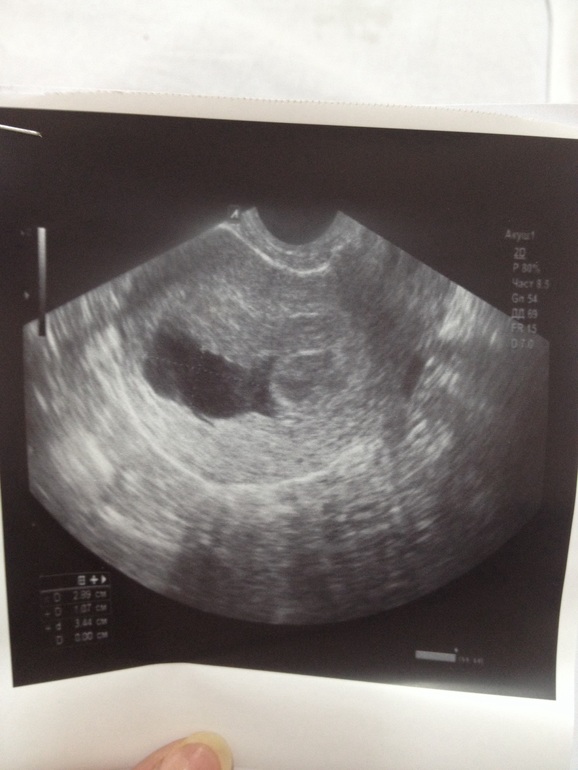

лежу в больнице на сохранении. Сегодня делали узи и врач сказала что плодного яйца нет!!!!!

Я съездила в платную сказали что плодное яйцо есть но эмбриона нет. Срок 6 недель 4 дня акушерских.

В воскресенье у меня размер пя был на 4 недели. А сегодня ни говорят вообще ни чего

а я о чем? нет плодного яйца и на данном снимке. может, в платной получше посмотрели и нашли ПЯ с анэмбрионией.. тут только повторное узи и хгч покажут.. кстати "аппарат".

У меня 22 числа делали узи и было пя в матке и срок поставили 4 недели от зачатия. А сегодня они мне выдают что пя вообще нет.